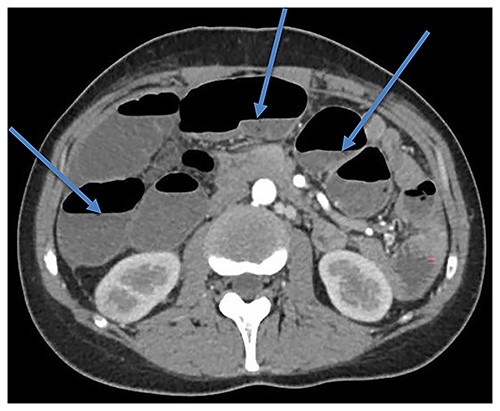

The patient was hospitalized several times due to partial bowel obstruction, which was managed conservatively. Abdominal radiographs and computed tomography (CT) scans revealed diffused dilated loops of small and large bowels (Fig. 1). Colon transit time was measured using radiopaque marker test. All markers remained in the bowels 5 days after the ingestion of them. Colonic hypomotility was diagnosed. As the patient was incapacitated by symptoms and did not respond to conservative treatment, subtotal colectomy was performed. Histopathological examination revealed abnormal layering of colonic muscularis propria. Both inner and outer muscular layers were very thin and inadequate (Fig. 2). Nevertheless, the symptoms of pseudo-obstruction persisted and the patient underwent another surgery. Sigmoid resection with preventive ileostomy was done. Histopathological examination showed the same abnormal changes of the colonic muscular layer. Few months later, preventive ileostomy was closed and ileorectostomy was performed. However, adhesive post-operative small bowel obstruction complicated patient’s recovery. Relaparotomy and adhesiolysis were done. After the last surgery, the patient still complained of abdominal distension and constipation. Colonoscopy disclosed anastomotic stricture, ~5 mm in diameter (Fig. 3). Endoscopic dilation was done, but the patient complained of the same symptoms few weeks after the procedure. Endoscopy was performed again and it showed an anastomotic stricture. Endoscopic dilation was done. This procedure was repeated with stent placement for a few more times due to recurrence of anastomotic stricture. Moreover, the patient still complains of constipation. Constipations are associated with abdominal distension and pain and just laxatives and enemas bring some relief for the patient. The patient continues follow-up and endoscopic treatment (repetitive dilatations) at a medical centre in the USA.

CT scan showing bowel dilatation (air-fluid levels are marked with arrows).